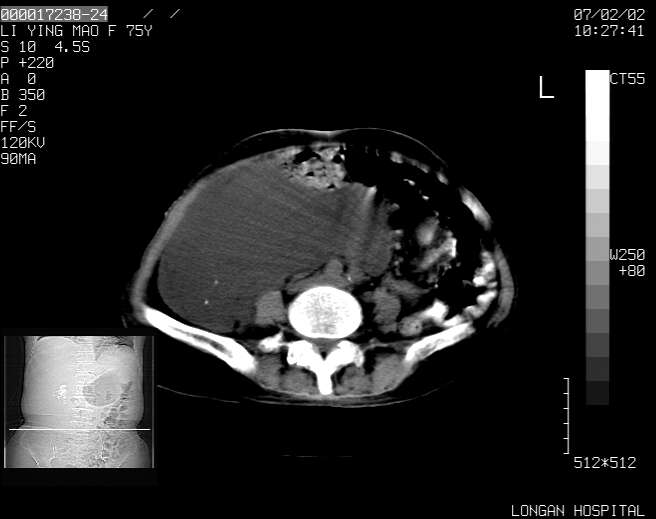

以下是引用dyqct在2007-2-10 8:53:00的发言:[br]考虑:1、肝脏多发囊肿[br] 2、左肾囊肿,右肾多发结石并积水。[br] 3、右胸少量积液。[br] 4、右肾周包裹性积液或淋巴管瘤(有见缝就钻的征象、薄隔、小结节状钙化)?[br] 5、腰椎动脉瘤样骨囊肿?[br] [br] [br]